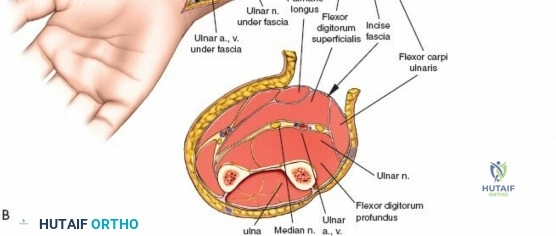

Exposure and Release of Deep Volar Compartment: This is the most critical and potentially challenging step. The median nerve and ulnar artery lie deep to the superficial flexor muscles.

- Median Nerve Protection: Retract the FDS radially. The median nerve typically lies beneath the FDS. It must be carefully identified and protected.

- Ulnar Nerve and Artery Protection: The ulnar nerve and artery run along the ulnar border, deep to the FCU. They are usually not directly in the field of the primary fasciotomy, but their fascial envelopes should also be released.

- Accessing the Deep Compartment: Separate the FDS radially from the FCU. Retract the FDS radially and the FCU ulnarly. The deep volar compartment, containing FDP, FPL, and PQ, is now accessible. The fascia overlying the FDP and FPL must be meticulously incised longitudinally. This deep release is crucial for adequate decompression.

This image illustrates the deeper dissection. The superficial flexor muscles (FDS) are retracted, exposing the median nerve and the underlying deep volar compartment. Note the care taken to protect the median nerve.

The median nerve and ulnar artery/nerve must be completely unroofed to ensure adequate decompression. This often requires releasing the entire carpal tunnel proximally to ensure distal decompression of the median nerve.

This detailed view highlights the median nerve (retracted by the yellow vessel loop) and the extensive release required, extending distally to encompass the carpal tunnel, ensuring complete decompression.Ensure that the deep fascia separating the FDS from the FDP and FPL is completely released. The anterior interosseous nerve and artery lie on the interosseous membrane and should also be decompressed by releasing the fascia overlying the deep flexors.

Further meticulous dissection showing the complete release of the deep volar compartment, with all muscle bellies visibly decompressing. Neurovascular structures are clearly identified and protected.